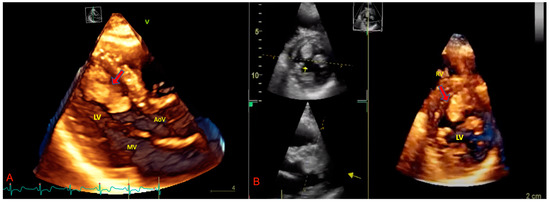

3. The Role of Echocardiography in pSTS-h